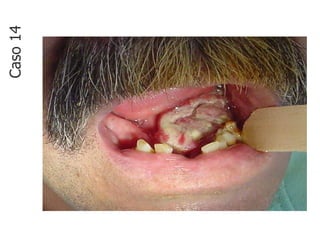

Caso

14

• Lesão fundamental: úlcera

• Localização: soalho bucal

• Quantidade: única

• Tamanho: 5,0 cm x 3,0 cm

• Borda: bem delimitada, elevada e

• endurecida

• e elevada

• Cor: branca

• Base: séssil

• Aspecto superficial: irregular

• Em soalho bucal nota-se lesão úlcero-vegetante,

esbranquiçada, única, bem delimitada, com base

séssil, superfície irregular e bordas elevadas que

mede aproximadamente 5,0 x 3,0 cm em seus

maiores diâmetros.

CASO 14 - Descrição